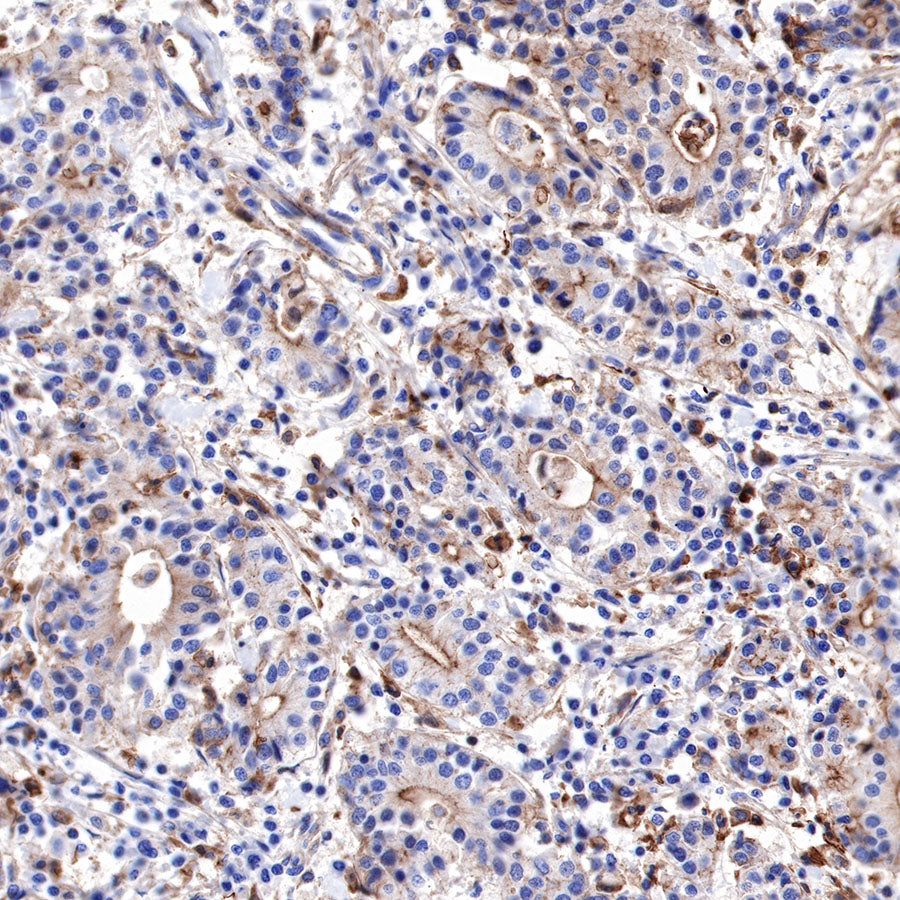

IHC shows positive staining in paraffin-embedded human pancreatic cancer. Anti-α-Actinin-1 antibody was used at 1/2000 dilution, followed by a HRP Polymer for Mouse & Rabbit IgG (ready to use). Counterstained with hematoxylin. Heat mediated antigen retrieval with Tris/EDTA buffer pH9.0 was performed before commencing with IHC staining protocol.